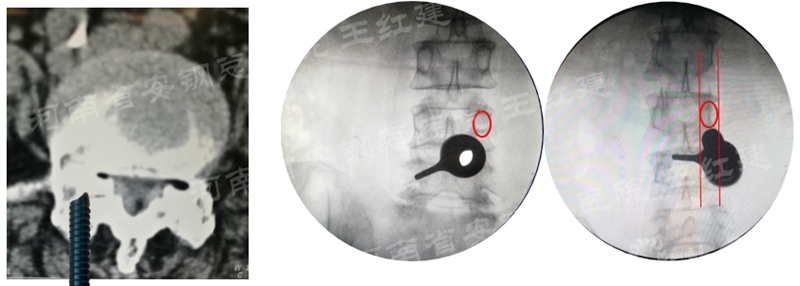

应用通道技术进行植入融合时,首先要更换工作套管,通过枪钳、抓钳的应用处理椎间盘,接着进行自体骨或同种异体骨及cage植入,并通过C臂透视确定试模型号放置融合器,最终完成植骨融合。

确定融合器位置

四、经皮螺钉技术固定

在固定的步骤可以先期进行经皮螺钉置入,再进行融合器的置入,进而实现充分固定。

椎弓根植入加压固定